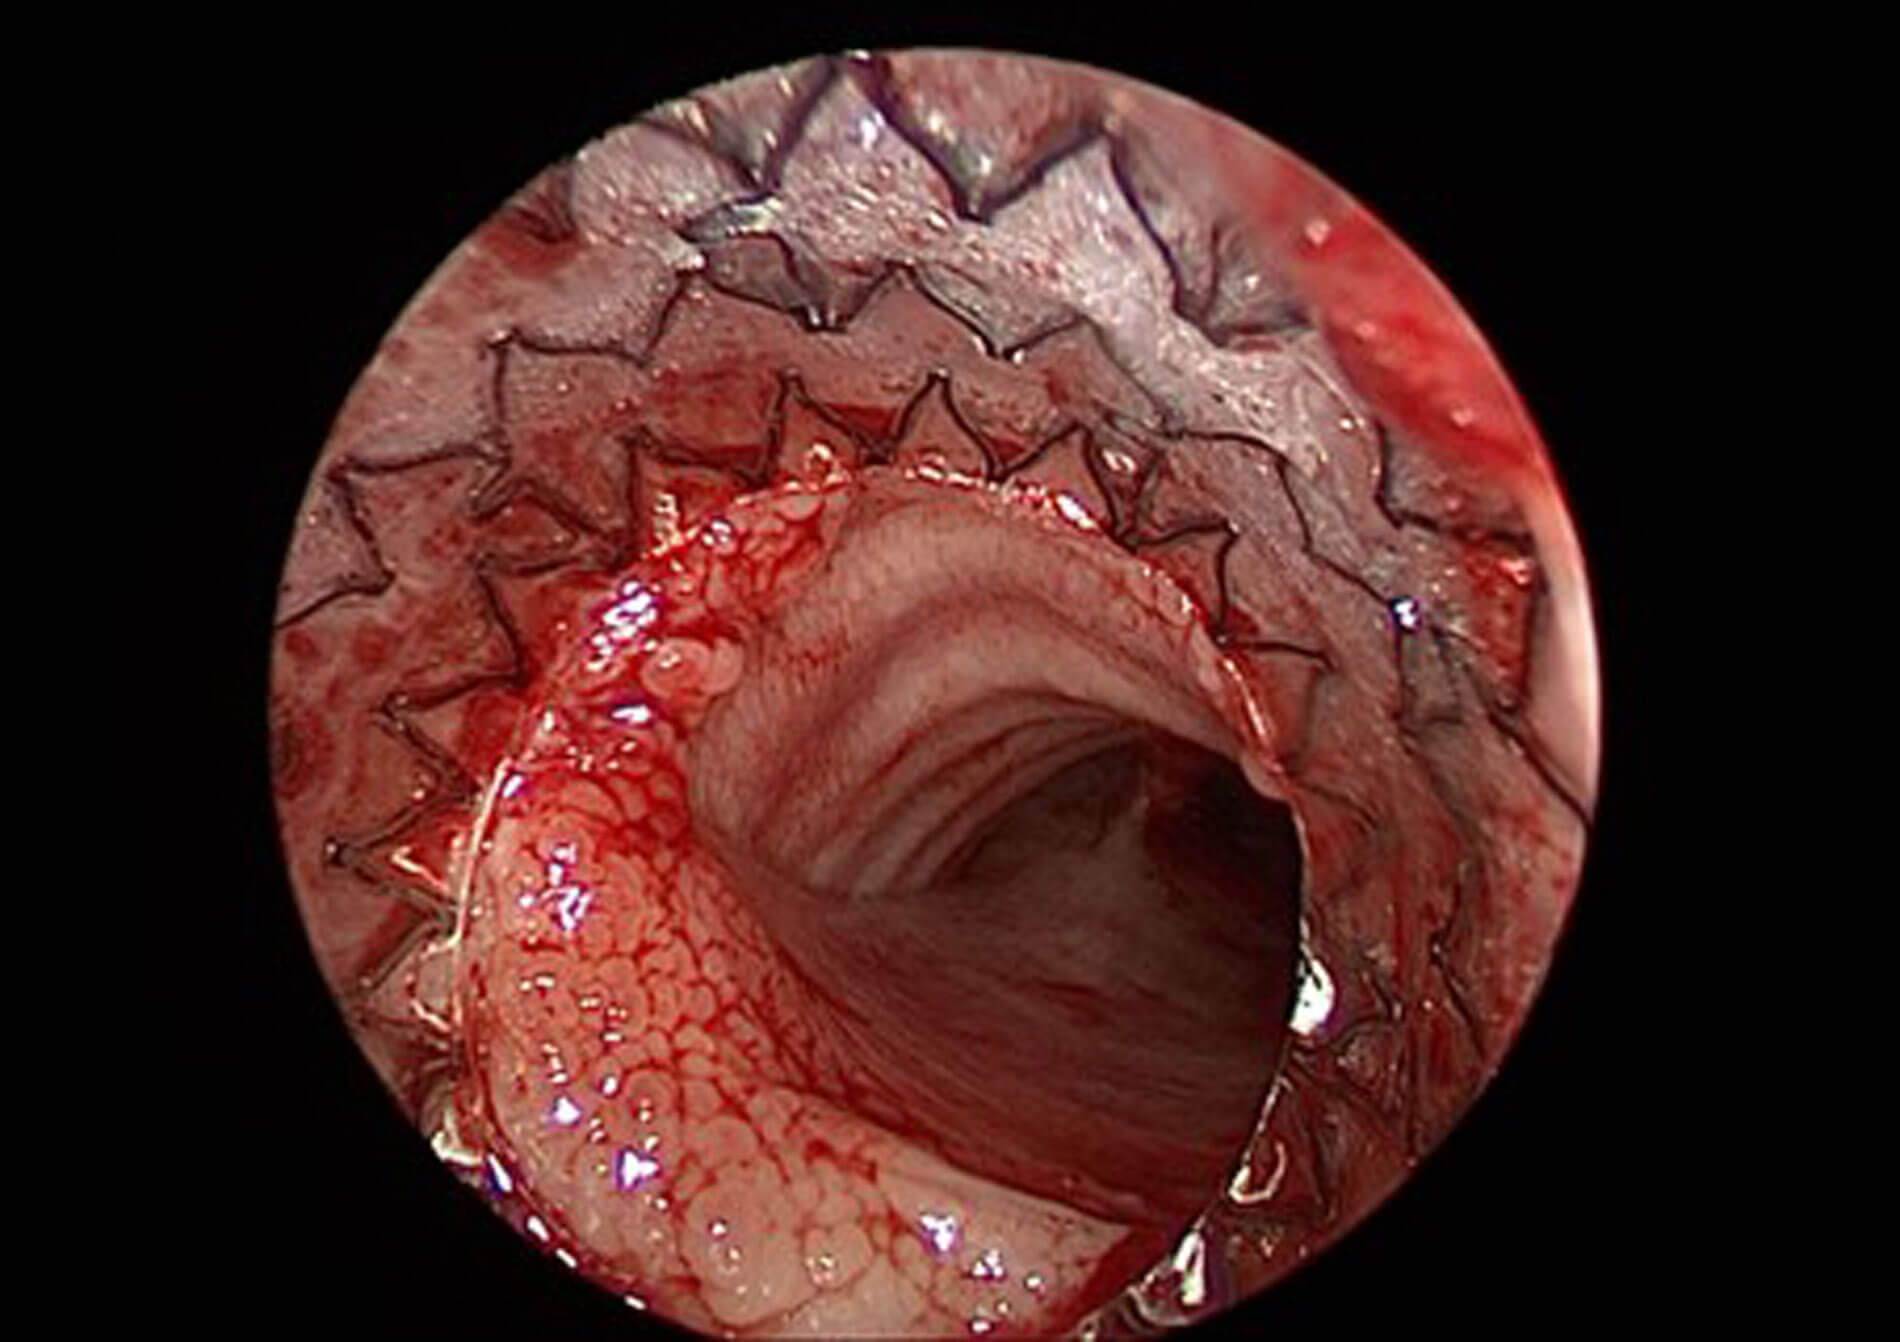

Figure 4. Endoscopic view of airway following AERO-stent deployment for severe malacia.

Intratracheal stents have been used to treat severe malacia, stenosis or compression of the airway when all other options have been exhausted. They are associated with a significant number of complications including granulation formation, migration, and perforation, and should only be used as a temporary measure. Traditional stents have included metal, soft silicone, and biodegradable self-expanding devices. The AERO-stent by Merit Medical is a completely covered self-expanding nitinol stent which has proved an attractive option for these difficult cases (Figure 4). The stent is deployed endoscopically using a pre-loaded delivery system; radio-opaque tip allows for accurate and precise checking of placement.